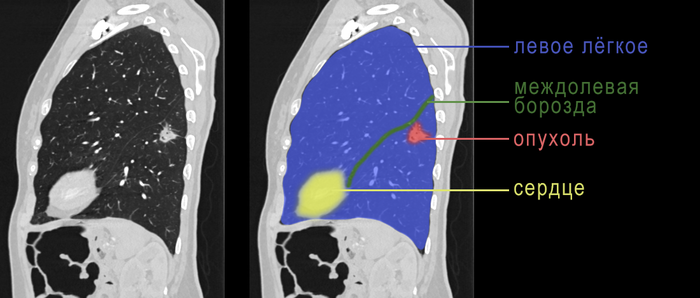

У второго пациента в 2010 году уже был рак желудка, по поводу которого успешно проведено хирургическое и химиотерапевтическое лечение. Пациент жив на протяжении 11 лет. Однако коронавирусная инфекция принудила пациента сделать КТ, на которой выявлено новообразование нижней доли левого легкого:

КТ-картина однозначно говорила нам о том, что опухоль недобрая. Поэтому мы не заморачивались с биопсией и сразу пошли на операцию. Пациенту выполнена нижняя лобэктомия слева, то есть удаление нижней доли левого легкого, что составляет половину от легкого и 25% всего легочного объема. При гистологическом исследовании у пациента диагностирована первичная аденокарцинома легкого без метастазов внутри легкого и в медиастинальных лимфатических узлах, то есть речь идет о раке легкого I стадии. Пациент победил второй рак в своем организме и отправился домой под динамическое наблюдение.

Теперь к пациентке. Женщина 60 лет. При плановом обследовании по данным флюорографии, а потом по данным КТ выявлена опухоль нижней доли левого лёгкого. Опухоль имеет характерные признаки злокачественности: лучистые контуры, тяжи к междолевой борозде, плевре (оболочке лёгкого):

Есть опухоль, значит нужно брать биопсию (хотя вопрос биопсии опухолей легких это отдельная тема). Так как новообразование расположено на периферии легкого, мы не можем достать его изнутри, то есть при бронхоскопии. Значит, нужно брать снаружи, то есть делать прокол грудной стенки специальной иглой (трансторакальная биопсия). У меня нет картинок того, как мы брали биопсию этой опухоли, но есть фото аналогичной ситуации. Процедура выполняется под контролем КТ, где видно ход иглы и глубину ее расположения.

При биопсии доказано, что опухоль представляет собой аденокарциному, то есть злокачественную опухоль из клеток желез. Теперь мы можем выставить показания к операции – нижней лобэктомии слева, медиастинальная лобэктомии. Что это означает? Это означает, что нам нужно удалить нижнюю долю левого лёгкого (50% от левого лёгкого) и лимфатические узлы, потенциально содержащие в себе метастазы. Для левой стороны это бифуркационные, субаортальные и парааортальные лимфатические узлы. Опухоль небольшая, признаков метастазов внутри легкого и в лимфоузлах у нас нет, значит клинически мы выставляем I стадию заболевания. При I стадии опухолей лёгких мы имеем право сделать операцию торакоскопически, то есть без большого разреза.